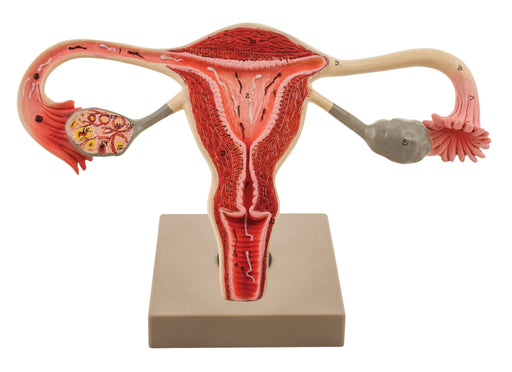

Eisco 3x Life-Size Human Female Reproductive System, Cross Section

Enlarged approx. 3 times. Enlarged approx. 3 times. This model represent the frontal section through female genital organ. Mounted on base. Numbere...

View full detailsAM0360 -